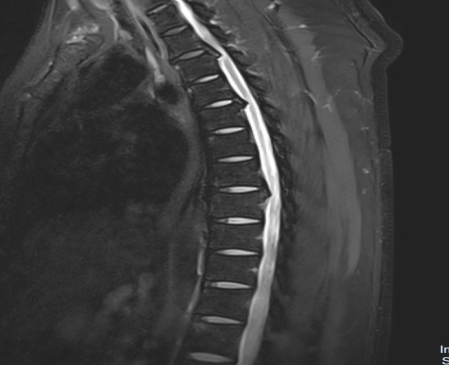

入院后,國文醫(yī)院骨科迅速組織多名專家會診,并為吳先生完善了頸椎及胸椎的 MRI 檢查。結(jié)果顯示,吳先生的頸椎及胸椎多階段嚴(yán)重椎管狹窄,脊髓壓迫超過 50%,情況十分危急。經(jīng)過骨科專家團(tuán)隊(duì)的綜合會診及評估,最終為他制定了一套個性化的治療方案,包括頸椎后路單開門椎管減壓頸椎融合內(nèi)固定術(shù),以及胸椎間盤切除伴椎管減壓胸椎植骨融合內(nèi)固定術(shù)。在完善術(shù)前檢查、確認(rèn)無手術(shù)禁忌后,骨科主任呂國福如期為吳先生實(shí)施了手術(shù)。

手術(shù)涉及頸椎及胸椎多個階段,操作難度極大。專家團(tuán)隊(duì)采用 “蠶食法” 減壓,分塊去除增生韌帶,最大程度減少對脊髓的損傷;同時運(yùn)用椎弓根螺釘固定技術(shù),確保手術(shù)部位的穩(wěn)定性。

頸椎及胸椎管狹窄在 40 - 60 歲長期伏案工作者,以及有脊柱退變家族史者中較為高發(fā)。其典型癥狀表現(xiàn)為進(jìn)行性下肢無力、胸腹部束帶感、步態(tài)不穩(wěn)如 “踩棉花”。在治療選擇上,單階段狹窄可考慮微創(chuàng),多階段狹窄則開放手術(shù)更為徹底;若合并脊髓信號改變,建議盡早手術(shù)。